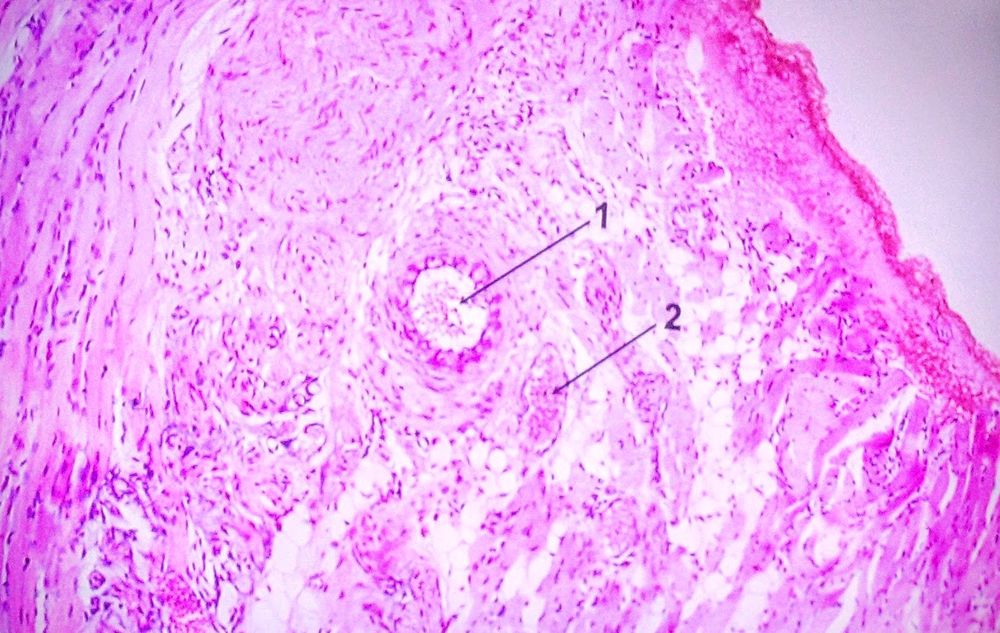

Question 1

Question

Label this Image.

Image:

dac2c85b-f5e9-423f-ab3a-9e91e0dd3a58 (image/jpeg)

Answer

Artery and vein of muscular type